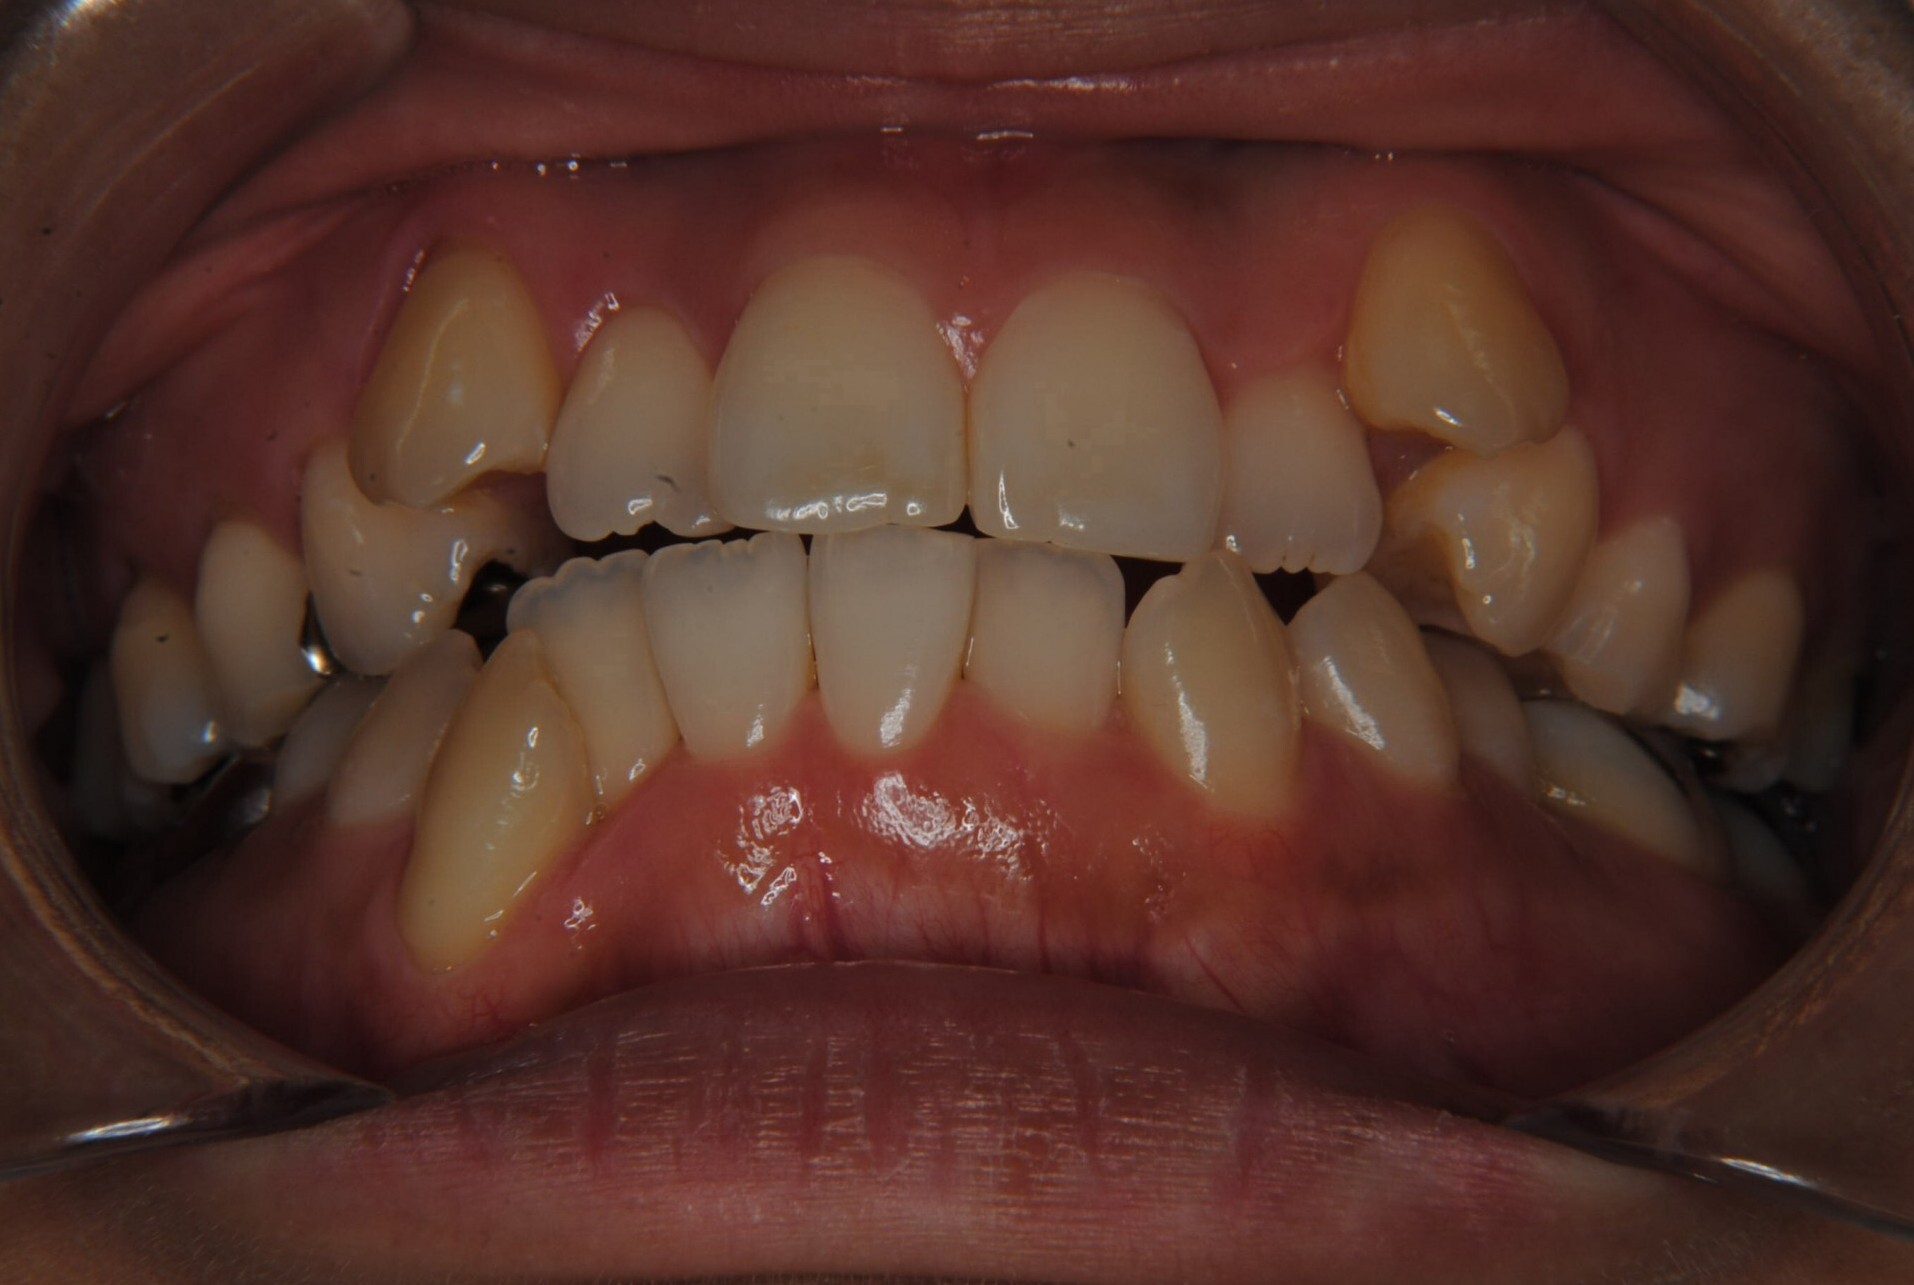

②診断名:AngleⅠ級叢生

④治療に用いた主な装置:マルチブラケット装置(T21ブラケット)

⑤抜歯部位:上下左右第一小臼歯

⑥治療期間:1年7ヶ月

⑧リスクと副作用:マルチブラケット装置(T21ブラケット)を初めてつけてから4日間、食事の時におもに前歯が少し痛かったとのことでした。治療後のエックス線写真で、歯根吸収はほとんど観察されず、歯肉を診ると残念ながら下顎前歯部に歯肉退縮(ブラックトライアングル)が生じていました。しかし、通常下顎前歯部は下唇に隠れてむき出しにはなっていないので、ご本人はあまり気にされていないご様子でホッとしています。